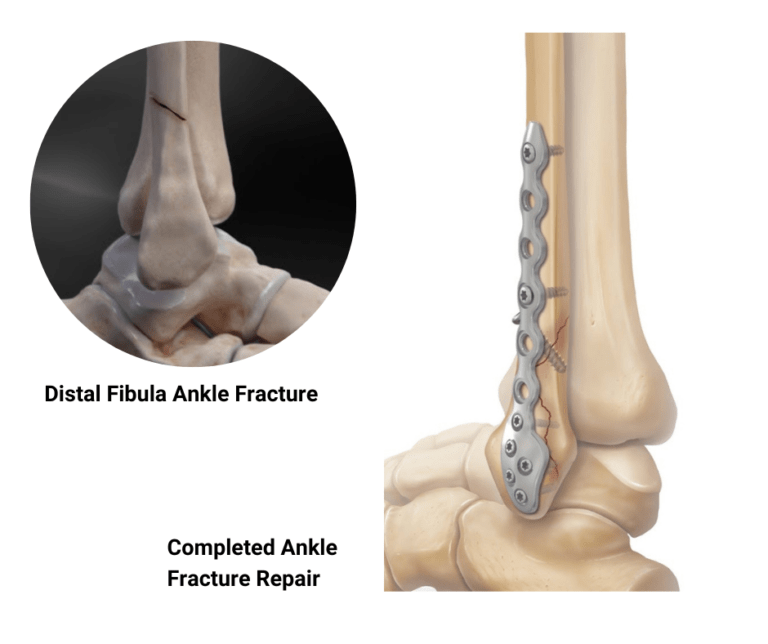

Структура и анатомия синдесмоза: научные иллюстрации